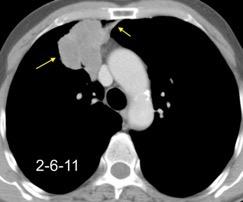

Síndrome de afectación postcardiaca (postcardiac injury)

Post infarto 1-7 % (Dressler)

Trauma cerrado Implantación marcapasos

Cirugía cardiaca. 17-31% (Post.pericardiotomía)

3707 pacientes 29 Derrames (0,78%) > de 25% del hemitórax

Todas menos 2 Izdos.

Angioplastia

By-pass coronario 21-10-03